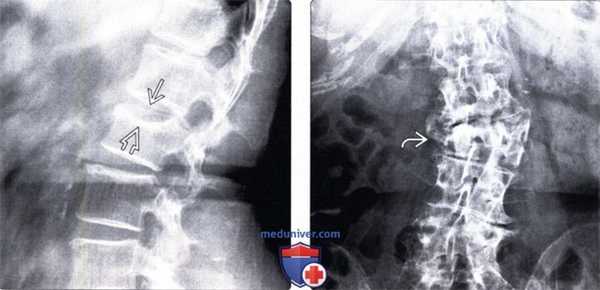

(Слева) На сагиттальном Т1-ВИ определяется чашеобразное вдавление верхней замыкательной пластинки позвонка у пациента с остеопорозом. Линия перелома, характеризующаяся низкой интенсивностью сигнала, расположена сразу же под замыкательной пластинкой. Пациенты с остеопорозом часто отмечают острое начало болевого синдрома после минимальной травмы либо вообще при отсутствии таковой.

(Справа) STIR МР-И: взрывной перелом Т12 и компрессионные переломы Т10 и Т11. При компрессионных переломах задняя покровная пластинка остается интактной.